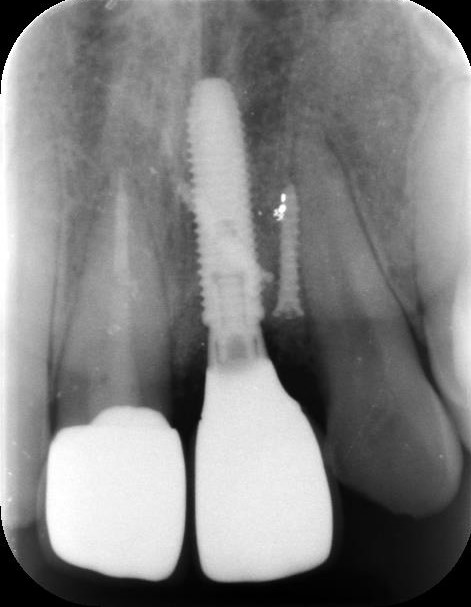

治療前レントゲン

治療前レントゲン

治療後レントゲン

治療後レントゲン

| 主訴 | 前歯に綺麗なインプラント治療を希望。前歯のインプラントは難しいと言われていて、何軒か相談したが数年迷っていた。できれば治療はしたいが、問題なく綺麗にインプラントができるか相談したい。 |

|---|---|

| 年代・性別 | 30代 男性 |

| 治療部位 | 上顎左側 1 |

| 治療費用 |

インプラント手術料 300,000円 |

| 手術回数 | 1回 |

| 治療期間 | 3ヶ月 |

| 手術時間 | 90分 |

| 治療回数 | 4回 |